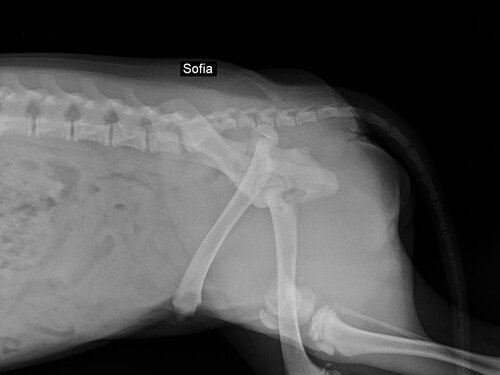

A primeira tia veterinária que me avaliou no dia 01/07, verificou através de exames de raio-x que eu estava com uma fratura muito feia na minha patinha traseira e disse que eu estava com muita dor. Ela falou que eu teria que ficar internada para tomar medicação e possivelmente realizar uma cirurgia na patinha. Além disso, com o resultado do exame de sangue, foi constatado que eu estava com anemia e alterações hepáticas.

No dia 03/07 tive uma consulta com o veterinário ortopedista e ele disse que aquele dodói não era uma fratura de atropelamento, e sim de ESPANCAMENTO. Ele também falou que eu precisaria fazer uma cirurgia para colocar implantes no ossinho da minha patinha e para a amputação da cabeça do fêmur. A tia que me resgatou perguntou ao ortopedista se eu ficaria com algum problema de mobilidade e ele disse que não devo ficar, mas que o ideal é eu fazer fisioterapia pós operatória.